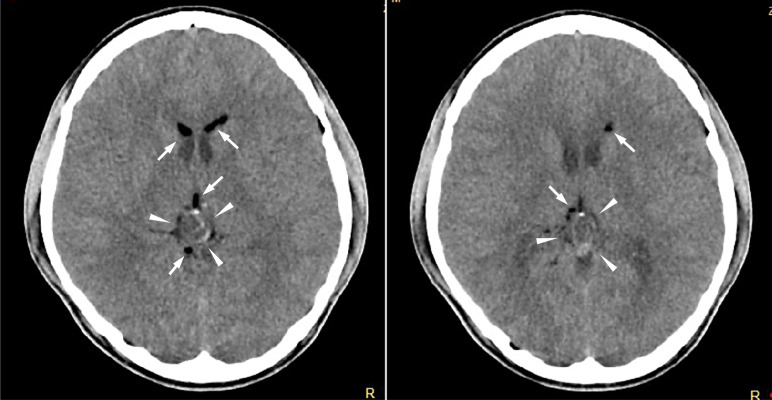

Case presentation: A 15-year-old boy presented with a 2-month history of persistent headaches. Computed tomography revealed a calcified mass lesion in the pineal region with low-density areas in the lateral ventricles. Magnetic resonance imaging (MRI) demonstrated a complex lesion in the pineal region and high T1 signal intensity bilaterally in the anterior horns of the lateral ventricles, suggestive of a ruptured teratoma. The patient underwent surgical resection. Postoperatively, he developed mild fever, severe headache, ocular pain, decreased vision, diplopia, and neck rigidity. Contrast-enhanced MRI revealed faint meningeal enhancement, consistent with aseptic meningitis. Symptoms gradually improved with steroid therapy.